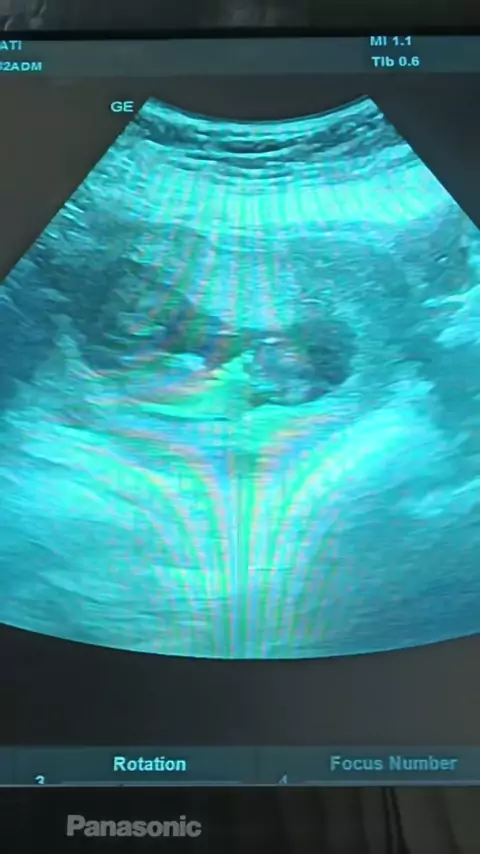

post ulang vidio asli nya masyaAllah speechless bgt SMP gemeter ngobrol m dokterš„° #pregnant #babytwins #hamilkembar #pragnancy #hamiltm2